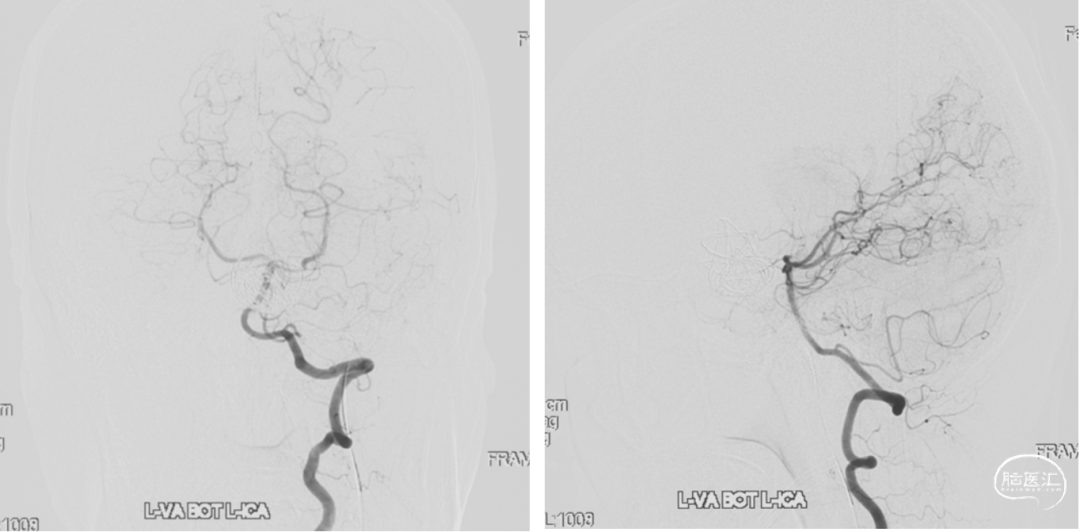

颈内动脉狭窄状况及闭塞试验

患者颞浅动脉、桡动脉较细,需行高流量+低流量搭桥维持大脑中动脉血流。

5. 术中:颈外动脉(ECA)-桡动脉(RA)-大脑中动脉(MCA)M2段搭桥,ICG显示血流通畅。

3.搭桥血流替代后孤立是治疗此类介入复发、血栓化巨大的动脉瘤的终极方式。只有孤立动脉瘤,使瘤体彻底的“去血化”后,结合切开减压,才能预防瘤体增大形成的占位效应。本例术前造影显示先后交通动脉开放代偿较差,故术者选择需高流量搭桥替代颈内动脉血流,保证充足脑血流灌注。下颌下隧道走行桡动脉,可缩短桡动脉所需长度,预防术后压迫。